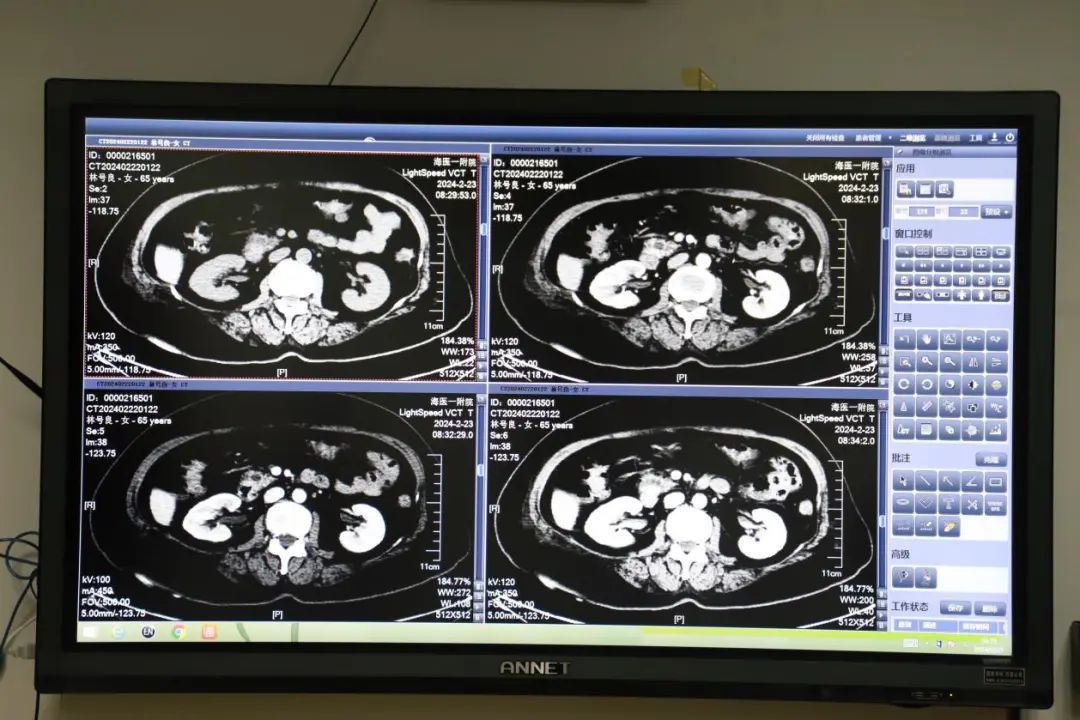

在详细听取了肝胆外科医师对患者病史、病情演变过程以及当前病情的汇报后,各专科专家围绕患者的基础状况、临床症状体征以及影像化验检查结果进行了深入的分析和讨论。他们以患者为中心,充分发挥各自的专业特长,共同为患者量身打造了科学合理、符合实际的个体化诊疗方案。